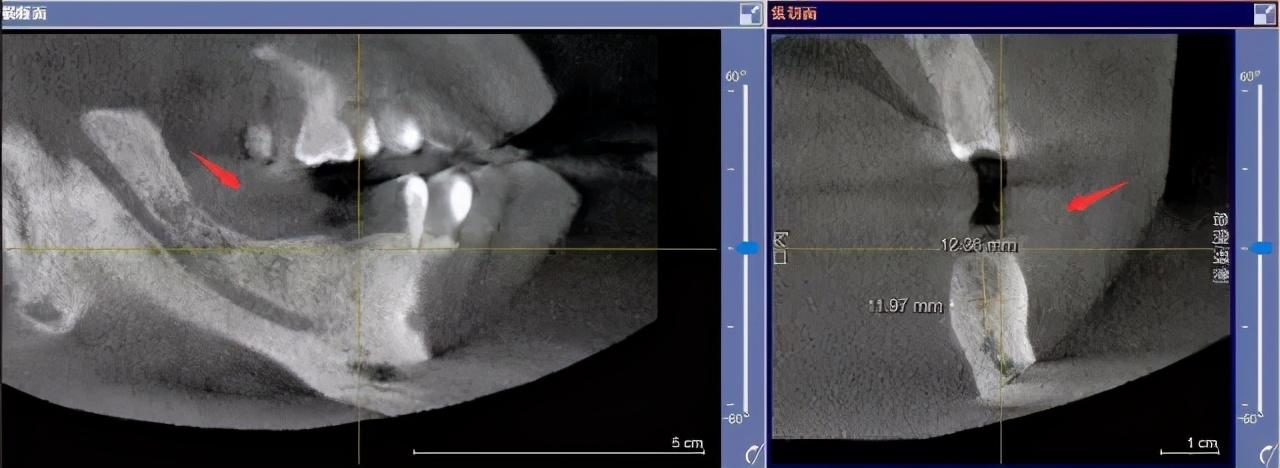

先要做一個(gè)口腔全景片、頜骨CT等

醫(yī)生根據(jù)機(jī)器成像查看口腔的具體情況,

是否有炎癥、牙槽骨的密度、吸收狀況

以及鄰牙組織、牙體組織等。

注明:此數(shù)據(jù)僅作模擬,不是確切種植數(shù)據(jù)。

如果僅靠雙眼大致估測口內(nèi)數(shù)據(jù),是無法得到的高度、寬度的,也無法確認(rèn)骨頭吸收多少,是否需要植入骨粉。

對后期手術(shù)有一定的影響。

通過全景片可以“解剖”牙齒測量,適宜的種植角度也可確定,健康有保障。